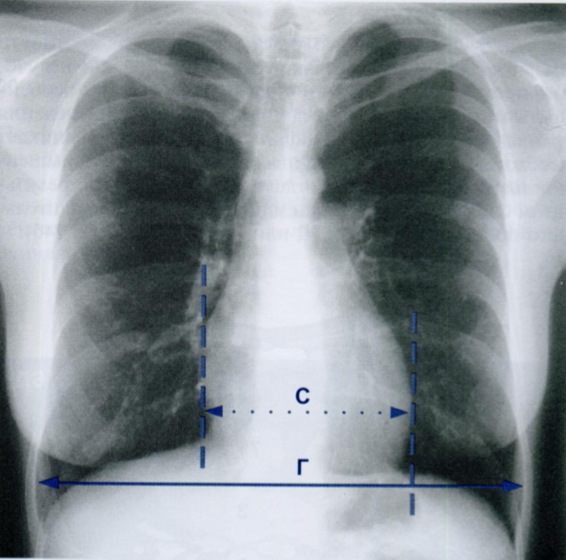

СГИ - это соотношение поперечной ширины сердца к ширине грудной клетки на уровне нижней апертуры.

Отмечаем точками наиболее выступающие тени сердца справа и слева (справа эта точка может быть выше - правое предсердие, чем слева - левый желудочек).

У взрослых данное отношение не превышает 0,5. То есть сердце не может быть больше, чем половина внутреннего диаметра грудной клетки.

СГИ в возрасте до года в норме до 0,65 и в 1-2 года - до 0,60.